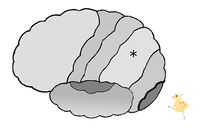

図は、左の大脳皮質を左から見た図です。

内耳からの聴覚性情報は、側頭葉の聴覚野へ届くことで「聞こえた!」と感じるのです。

大脳皮質の図において、*印は 前頭葉 頭頂葉 後頭葉 側頭葉 である。